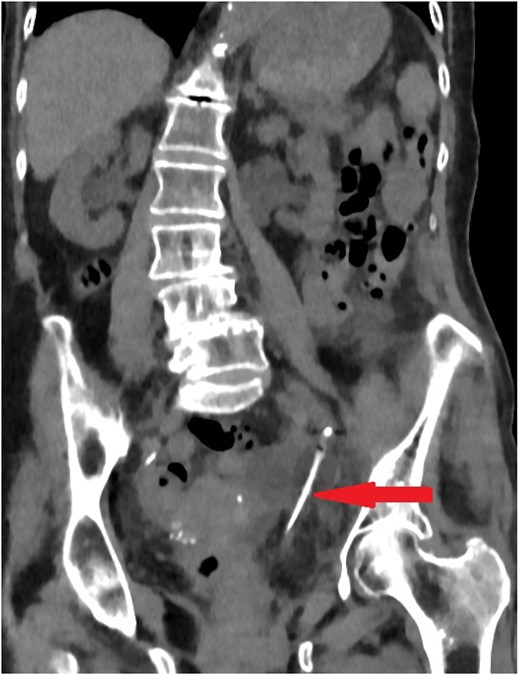

The old catheter was removed, and a replacement was inserted correctly into the bladder. The patient was managed conservatively with antibiotics. A further contrast CT was performed and showed mild extravasation of the contrast at the same level of the former catheter’s inflated balloon (Fig. 2). The patient improved clinically with conservative management, and her blood investigations remained stable. Follow-up contrast CT after 2 months was normal and showed no extravasation and no stricture (Fig. 3).

Coronal section of abdomen and pelvis contrast CT 2 weeks after the injury: Contrast flows normally without extravasation or stricture in the left ureter.